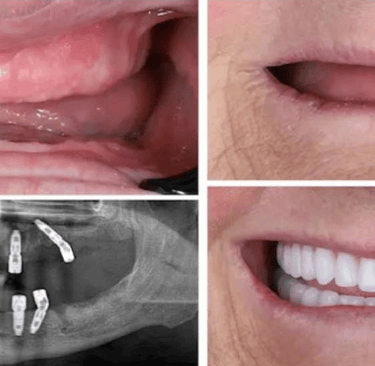

✅ Step 1: Consultation & Evaluation

Digital X-rays and oral examination.

✅ Step 2: Implant Placement

Titanium implant is placed into the jawbone.

✅ Step 3: Healing (Osseointegration)

Implant fuses with bone over few months.

✅ Step 4: Crown Placement

Custom-made tooth crown is fixed.

At Dr. Wadkar’s Dental Clinic, we specialize in replacing missing teeth with solutions that look, feel, and function exactly like natural teeth. Using the latest Digital Implant Workflow, we ensure every procedure is minimally invasive and highly predictable.

1. Single & Multiple Tooth Implants

Whether you are missing one tooth or several, we provide customized titanium or zirconia implants. Our approach focuses on preserving your natural bone structure and neighboring teeth.

2. Full Mouth Rehabilitation

For patients with significant tooth loss, we offer comprehensive full-arch restorations. Utilizing techniques learned from masters, we stabilize your entire smile with a few strategically placed implants.

3. Computer-Guided Implant Surgery

Leveraging the digital mastery we use 3D imaging to plan your surgery before we even begin.

● The Benefit: Smaller incisions, faster healing times, and pinpoint accuracy.

4. Bone Grafting & Sinus Lifts

If you’ve been told you don’t have enough bone for implants, we can help. Dr. Wadkar performs advanced bone augmentation to create a solid foundation for your new smile.